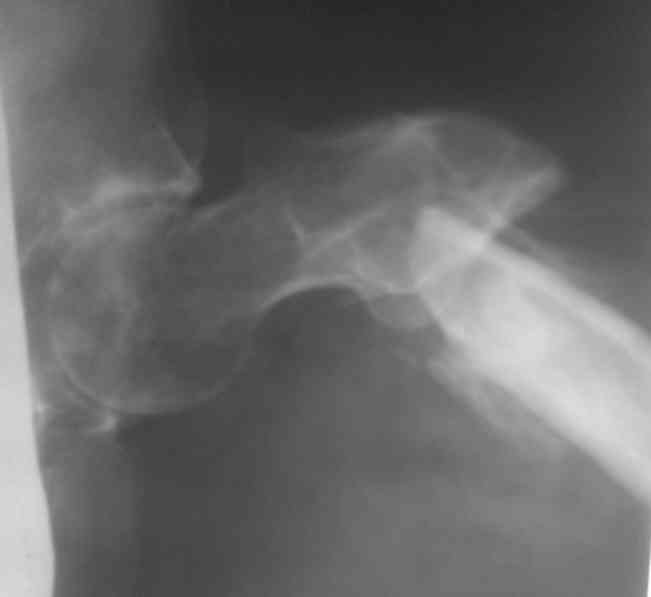

[Ortho] Лечение ложного сустава шейки бедра

Название темы- это произвольно!! Второй снимок прилагаю!!! Больница ЖД